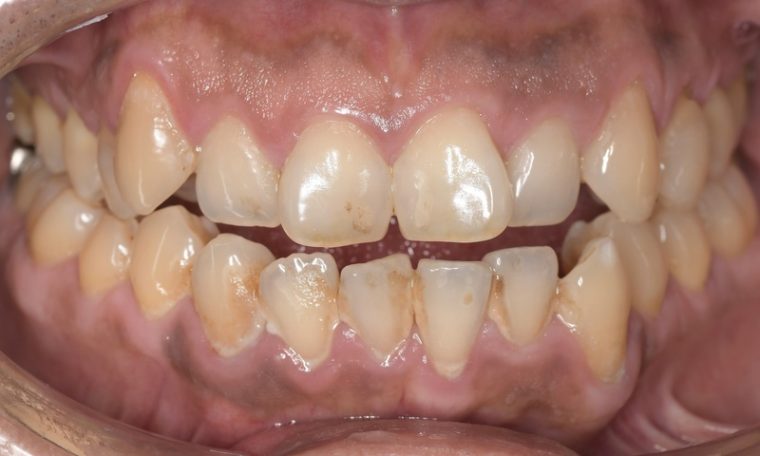

CASE 14

下顎before

下顎after

臼歯before

臼歯after

基本情報

| 年齢・性別 | 27歳・男性 |

|---|---|

| 主訴 | 歯石とりたい |

| 治療内容 | スケーリング |

| 治療期間 | 30分 |

| 治療費 | 約1,500円(保険診療) |

| リスク・副作用 | 知覚過敏、歯肉退縮、出血 |

| 治療方針 | 歯列不正でプラークがつきやすいため、TBIを行い定期的に歯石を除去していきます。 プラークコントロールが出来るようになったら定期検診でクリーニングを行っていきます。 |